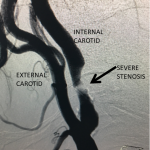

Figure 4.

Catheter angiography prior to angioplasty revealed critical stenosis (Figure 2). Angioplasty was therefore performed under local anesthesia with an embolic protection device deployed to catch any dislodged debris (Figure 3). After angioplasty, a stent was opened across the lesion to maintain long-term patency (Figure 4). Post-stent angiography showed smooth dilatation of the lesion. The patient’s aphasia continued to improve at his 6-week follow-up visit and duplex revealed no significant stenosis through the stent.